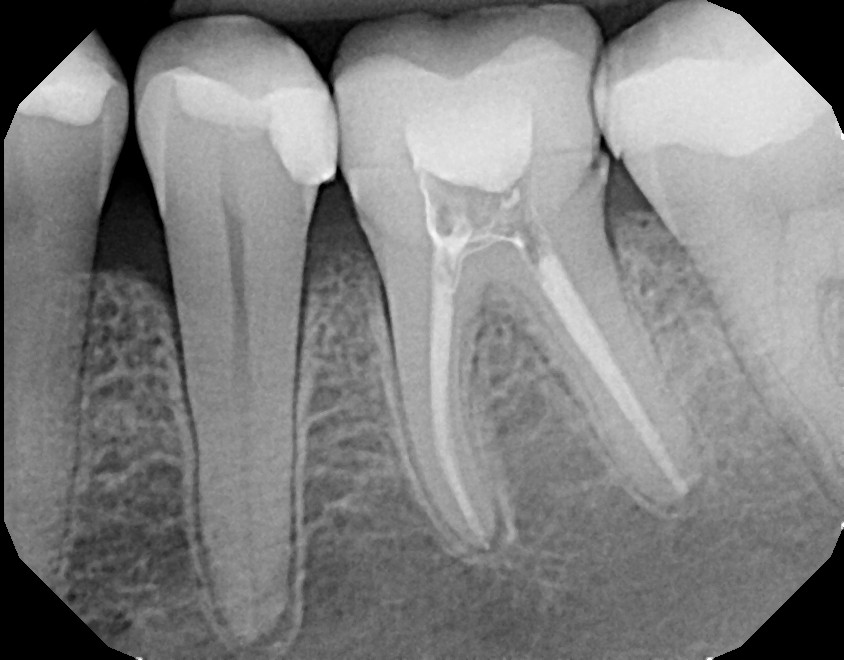

This first mandibular molar (tooth #19) developed decay from a lack of flossing or did not have all decay properly removed. An experienced general dentist can properly diagnose a cavity with 6 month check up exam and x-rays to avoid extensive work requiring root canal therapy and crown. Always ask your dentist for a consultation with a root canal specialist if you are uncertain of a possible developing tooth problem.